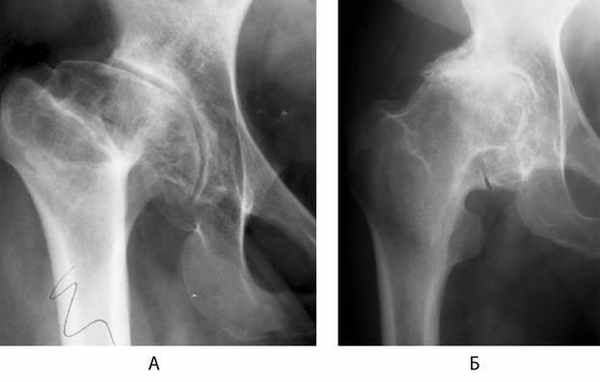

Клинически в начальной I стадии деформирующего артроза появляются боли в суставе после физической нагрузки. Иногда боли беспокоят как в коленном суставе, так и в поясничной области, поэтому больные нередко обращаются к невропатологу и лечатся от радикулита или от «отложения солей» в коленном суставе. Это отраженные боли при деформирующем артрозе тазобедренного сустава. Рентгенологически в начальной стадии можно обнаружить незначительные изменения в виде склероза субхондрального отдела вертлужной впадины.

При II стадии деформирующего артроза боли локализуются уже в тазобедренном суставе С иррадиацией в поясничную область и коленный сустав. Клинически наступает умеренная атрофия мышц бедра, ограничение отведения бедра в сторону, при движениях отмечается хруст в суставе, боль при пальпации в паховой области в проекции суставной щели. Сгибание и разгибание в суставе не ограничены. Рентгенологически отмечаются костные разрастания по краю вертлужной впадины, иногда деформация головки бедренной кости, могут быть дегенеративные кисты.

Рентгенологически отмечается сужение суставной щели, деформация головок бедренной кости, массивные костные разрастания но краям суставных поверхностей.